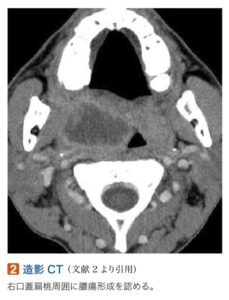

頸部造影CT:片側口蓋扁桃の腫大、中心部に低吸収の膿瘍

検査 造影CT:膿瘍腔の範囲や動脈の蛇行、喉頭浮腫を確認